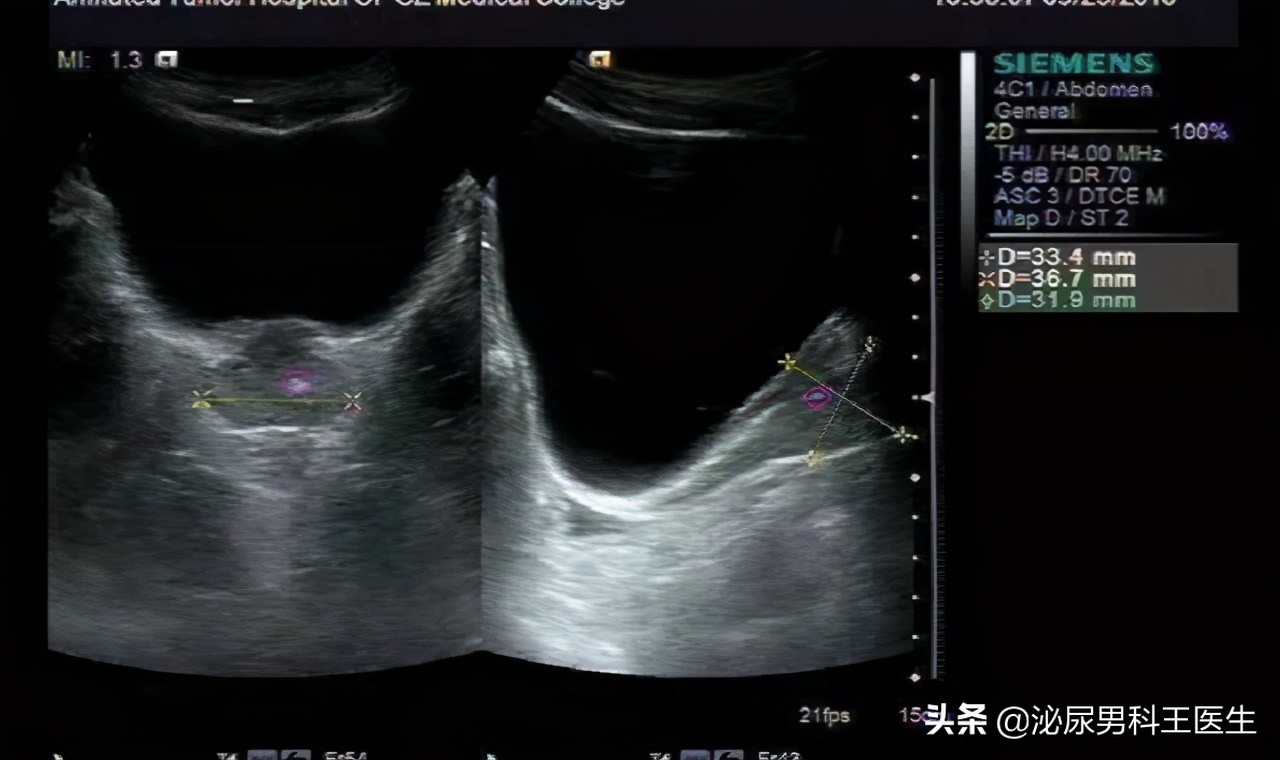

为了确定林先生是否的确患上了前列腺钙化,医生让林先生先去做一个超声检查。检查结果出来之后,医生拿到林先生的检查报告单,发现果然是前列腺钙化惹的祸。

超声所见 :前列腺42*30*23mm,包膜光滑,实质回声不均匀,内可见强回声光斑分布,测其一直径约5mm。双侧搞完附睾大小、形态正常,内部回声均匀,CDFI:未见异常血流信号。左侧精索静脉宽约1.9mm,异常精索静脉款约1.8mm。

诊断意见 :前列腺内钙化斑;左肾、膀胱、双侧*丸睾**、附睾未见明显异常。